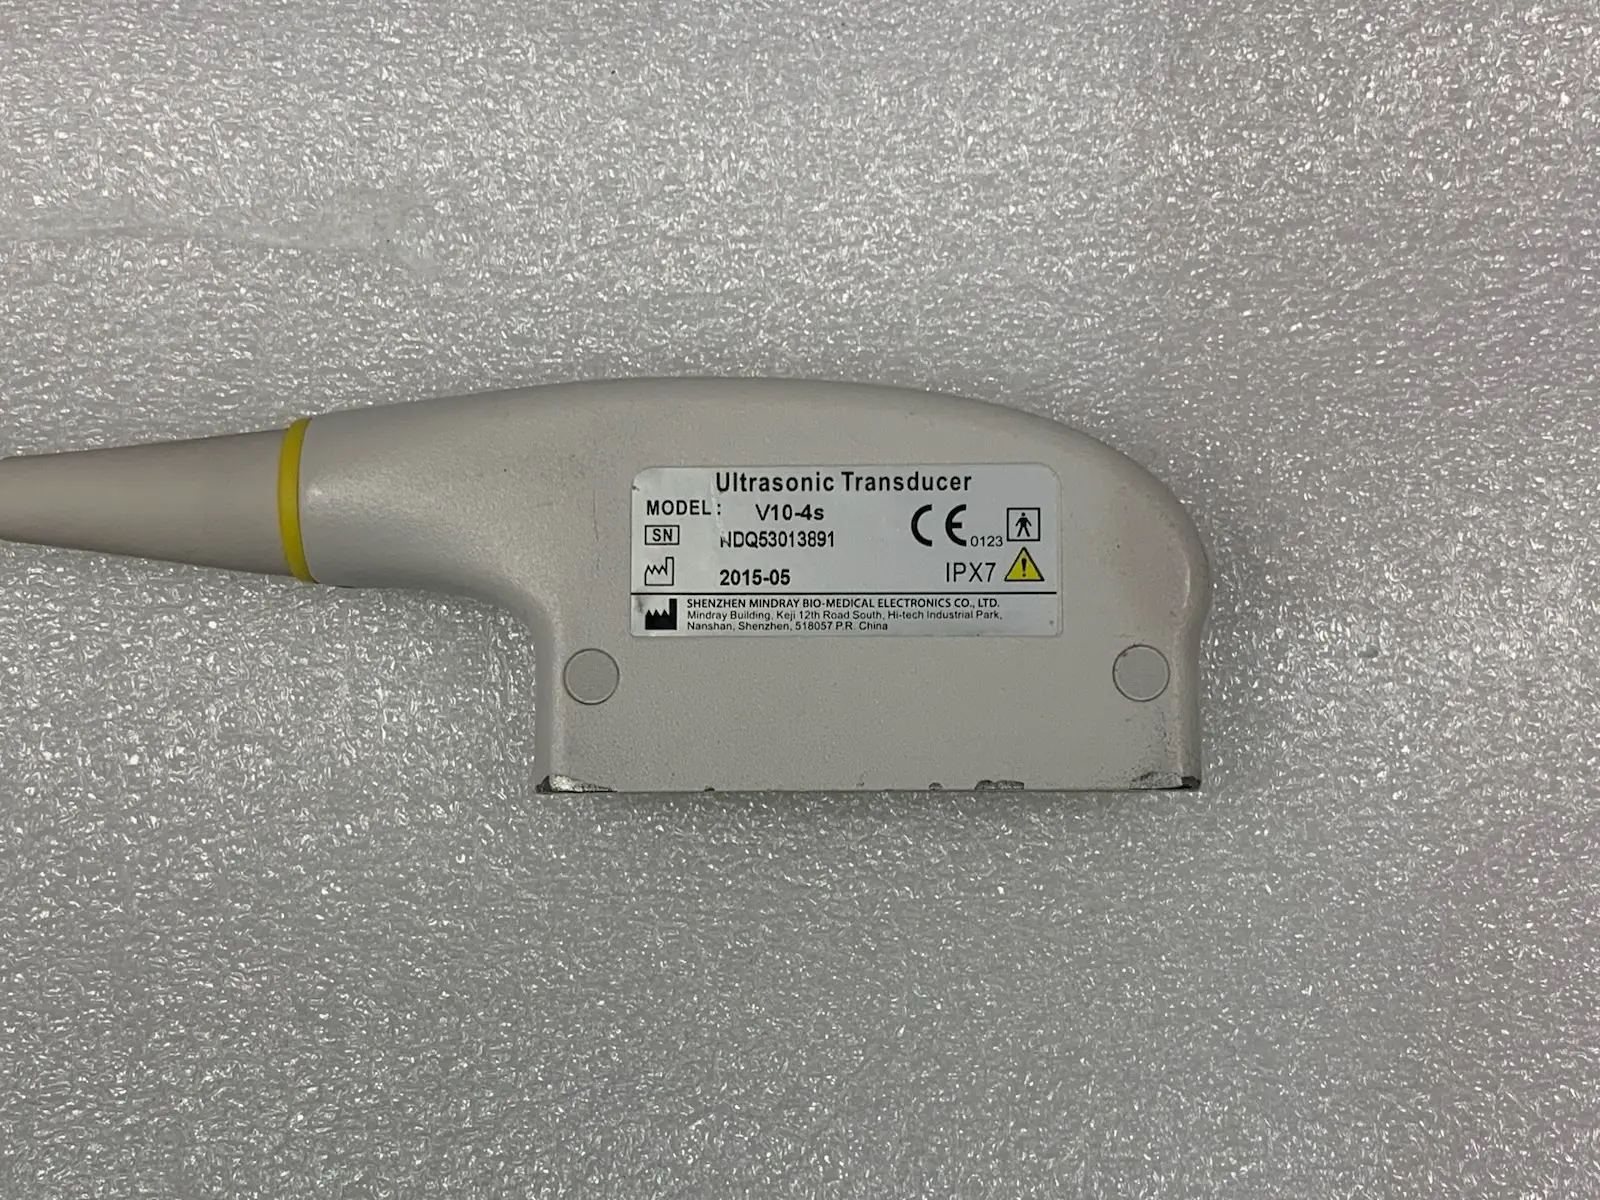

Brand: Mindray

Model: V10-4s

MPN: 023-000041-00

Frequency Range: 4.0 MHz – 10.0 MHz

Country of Origin: China. Tariffs may apply for US customers.

Photos of this listing are of the actual item for sale.